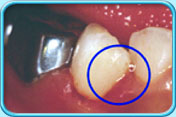

图中所见是一颗牙齿的牙颈部位因经受磨擦而耗损,并形成凹槽。补牙前

图中所见是牙颈原本耗损的部分以玻璃离子水门汀填补后的外貌。补牙后